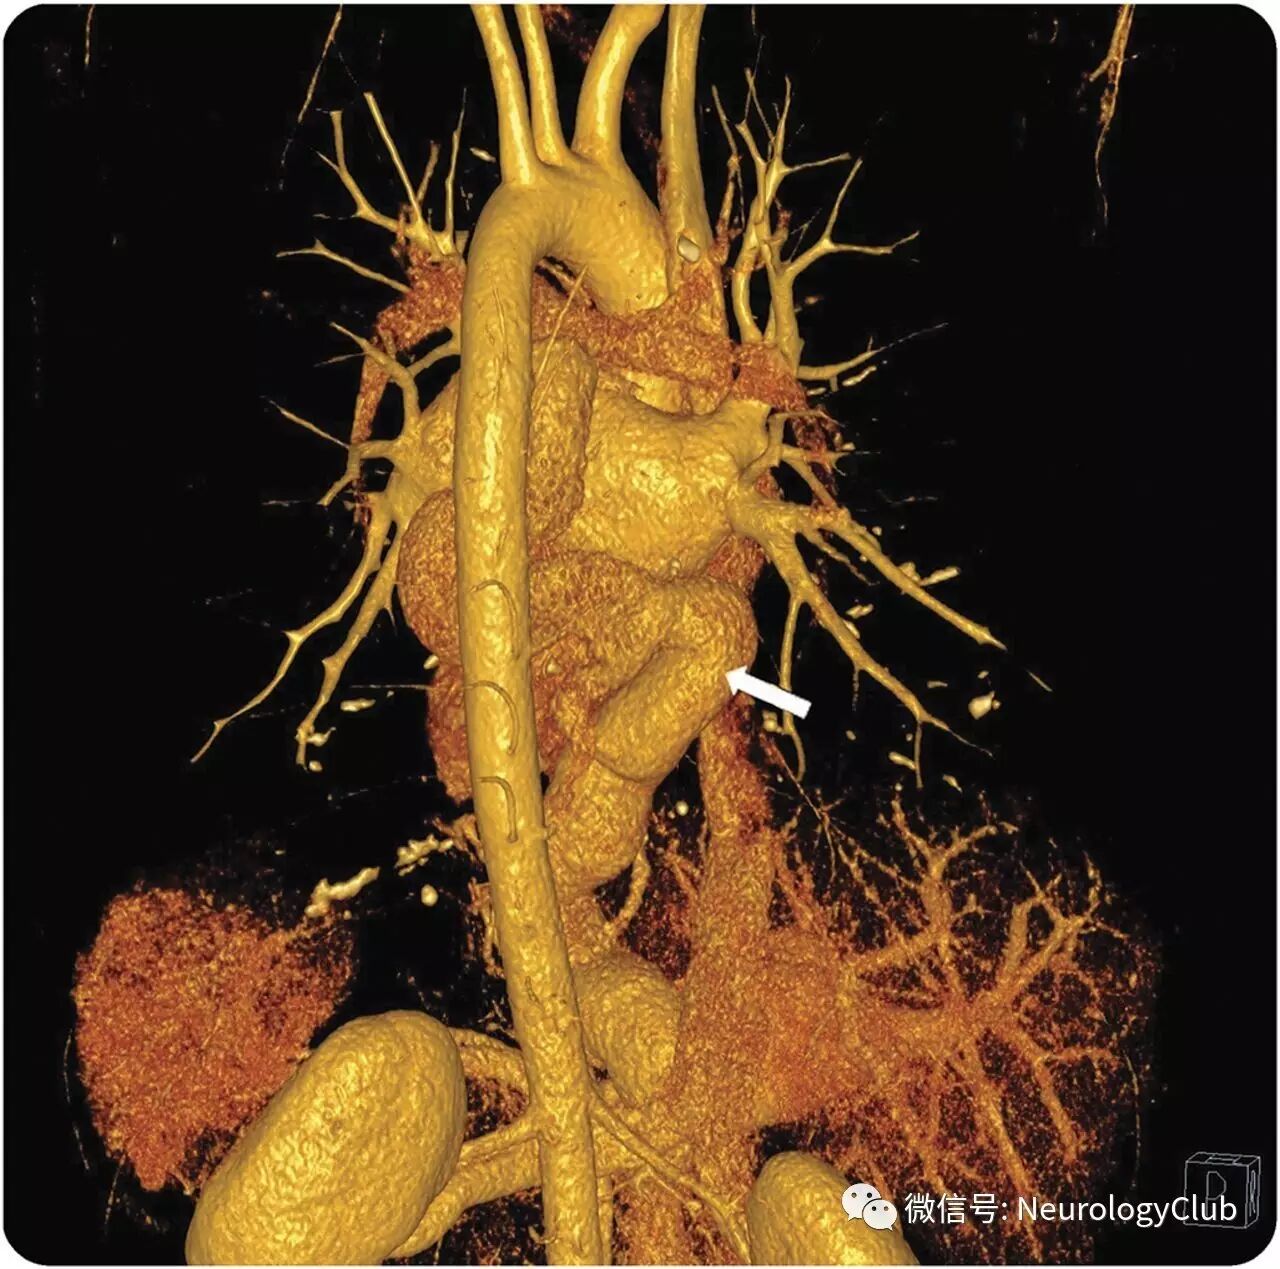

32岁男性,表现为意识模糊和复视。查体提示完全性垂直凝视麻痹伴相对保留的垂直前庭眼球反射,上视时会聚性眼震,交替性内收肥厚性反向偏斜,右眼外展受限伴内斜视,以及右侧肢体共济失调(视频)。MRI提示左侧丘脑旁中央梗死(图1)。垂直性凝视麻痹是因内侧纵束喙侧间质核损害所致。对侧内收受限符合假性外展神经麻痹,归因于下行中脑抑制会聚通路破坏。卒中机制被认为是一种罕见心血管畸形来源的反常栓子(图2)。

(图1:DWI提示左侧旁中央丘脑梗死[A],延伸至延髓喙内侧[B];年轻人这一部位丘脑梗死提示心源性栓子来源)